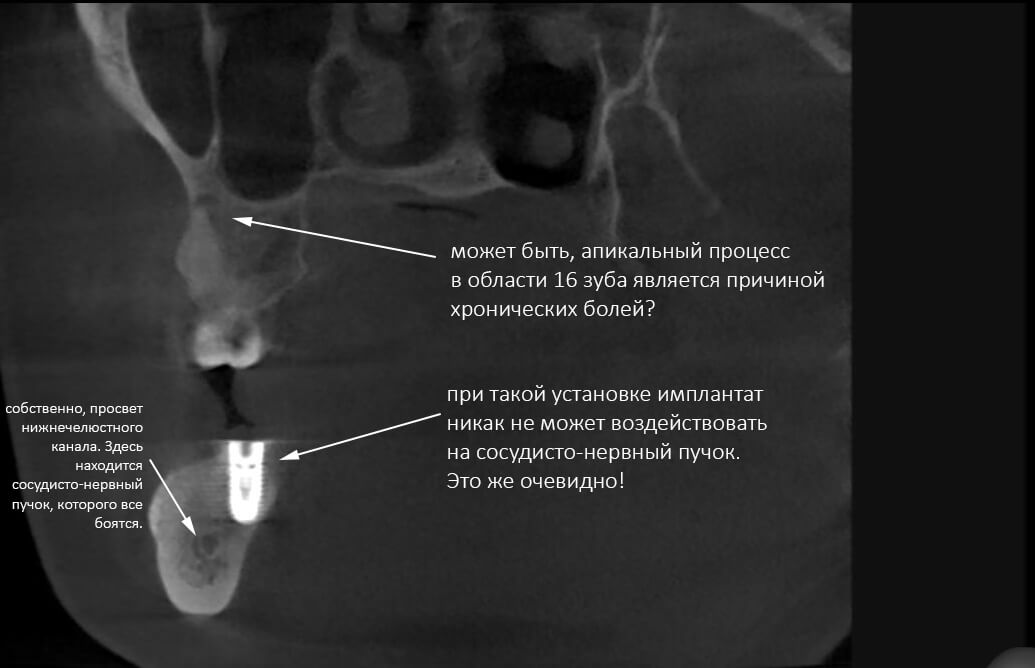

Однако ж, вернёмся к КЛКТ и пациентке, страдающей невралгией хроническими болями после установки имплантатов. Рассмотрим снимок более внимательно:

Любая из вышеозначенных и, при этом, визуализированных патологий могут быть причинами болевого синдрома. И, скорее всего являются таковыми. Как мне кажется, пока мы их не исключили, ставить неврологический диагноз, мягко говоря, преждевременно.